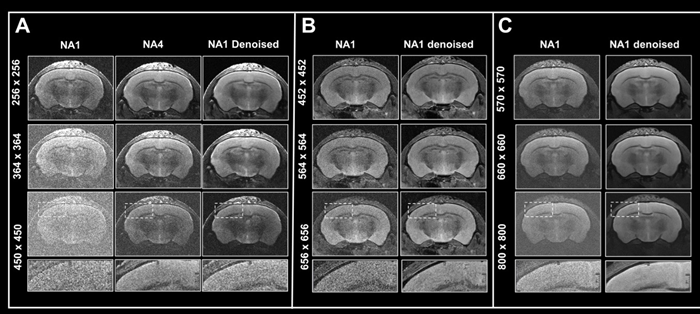

This article shows how Smart Noise Reduction may be utilized to reduce acquisition times while retaining image quality.

Figure 6. Boosting resolution. Ex vivo T2-weighted TurboRARE data of a fixed mouse head acquired at A) 3 Tesla, B) 7 Tesla, and C) 9.4 Tesla. All images were acquired with 0.8 mm (A) and 0.7 mm (B, C) slice thickness and with a field-of-view of 20 x 20 mm2 and the given matrix size using either no averaging or acquiring 4 averages. Images were reconstructed with no denoising (NA1 and NA4), or after denoising (NA1 Denoised) using a network Large, applying a pre-denoising level of 50 % and denoising level of 70 %. Image Credit: Bruker BioSpin Group

In Fig 6, axial T2-weighted TurboRARE images of a fixed mouse head taken at various field strengths are compared. Images were obtained with a fixed field-of-view of 20 x 20 mm2, slices that were 0.8 mm (3 Tesla) and 0.7 mm (7 and 9.4 Tesla) thick, and changing matrix sizes to produce images with various spatial resolution.

For images acquired at 3, 7, and 9.4 Tesla, the matrix sizes were raised by up to 1.8, 2.6, and 3.1 (compared to the reference protocols' matrix size of 256). These resolution upgrades cause a reduction in SNR for each image.

The loss in SNR can be accounted for by averaging, therefore extra data was collected using four averages.

A comparison of non-denoised averaged images and single averaged images that were denoised demonstrates that denoising reduces increased image noise at higher resolutions and produces images of comparable quality to those generated through averaging.

The advantages in image quality from denoising are greater with data recorded at 3 Tesla, when increasing resolution provides images that are more difficult to interpret, as opposed to data acquired at 7 and 9.4 Tesla, where SNR is naturally higher.

Nonetheless, images taken at 7 and 9.4 Tesla benefit significantly from denoising during reconstruction since the intrinsic higher SNR of these images may be used to pick smaller voxel sizes.

This shows that denoising allows for better resolutions within a given unit time by reducing the requirement for averaging. This can also be useful when averaging is neither desirable nor practical.